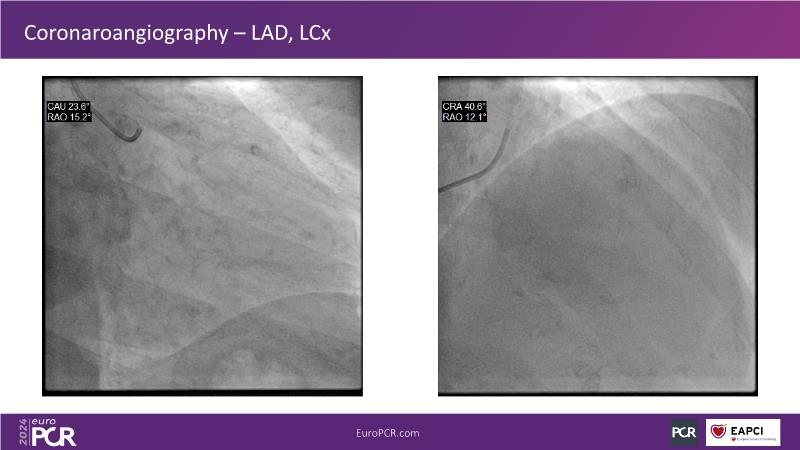

In this session, discover the effectiveness and safety of robotic PCI for both simple and complex lesions requiring additional devices like IVL, IVUS, laser, and FFR. Learn about the numerous benefits of robotics for patients and cathlab teams, including enhanced precision in wire navigation and stent positioning, full radioprotection, and reduced orthopedic injuries. Explore the growing interest in robotics within the interventional cardiology community, anticipate future technical advancements, and understand how AI will accelerate the integration of robotics and vice versa.